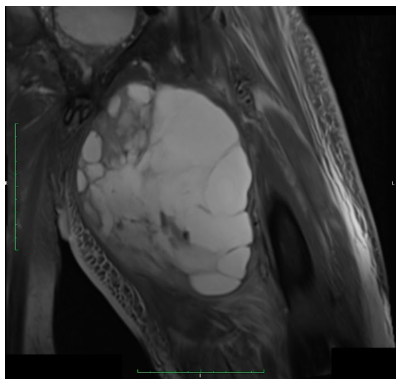

Radiographic imaging is used to help form a diagnosis of UPS. These include X-Ray, MRI, CT and Bone Scans

An example of an MRI is shown.